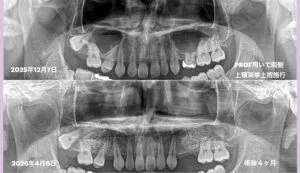

このような場合、上顎側壁よりアプローチを行なって、上顎洞内を底上げし、骨を造り上げる手術を行います。これが上顎洞挙上術です、昨年の12月に2例行い、この4月に評価を行いました。上顎洞内には、骨を造る骨芽細胞が多く存在し、組織工学に則って、①細胞、②成長因子、③骨補填材を配合し、組み合わせた生体材料を補填するのです。

当医院では、PRGF(成長因子)を使用します。これが重要です。PRGFを使用すると、未使用より約1.5倍創傷治癒が速まり、25%ボリュームが増大します。つまり通常は骨になるまで6ヶ月を要しますが、PRGFを使用すると、4ヶ月で造骨しインプラント埋入術が可能です。